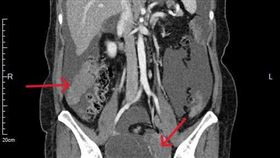

陳宗彥進ICU搶救處危險期 未來3天最關鍵

行政院前發言人陳宗彥擔任內政部次長期間,碰上新冠疫情...

2026/02/05 06:25

陳宗彥驚傳進加護病房 馬偕曝最新病況

行政院前發言人陳宗彥驚傳3日與友人聚餐時,突感身體不...

2026/02/04 22:35